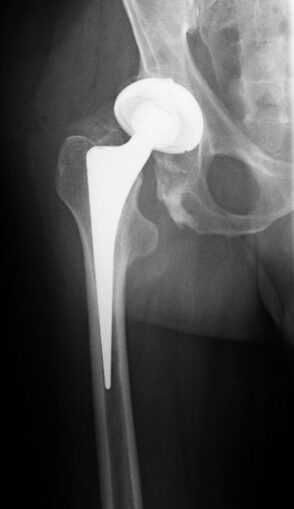

News has emerged from the NHS that there is a shortage of medical bone cement. It seems Heraeus Medical, the German company that supplies 90% of the cement that the NHS uses in hip and knee replacement operations, has had a serious packaging problem and has had to halt production at its main factory. It is expected that it will be at least two months before stocks are back to normal. In the meantime, the NHS is stopping routine operations and what stock it has will be used for priority cases such as accidents and falls. The NHS also says it will be using non-cemented options where possible. I only hope not too many people have to wait in pain.

“File:Hueftgelenk-Endoprothese.jpg”,

No machine-readable author provided. – Licence CC BY-SA 3.0